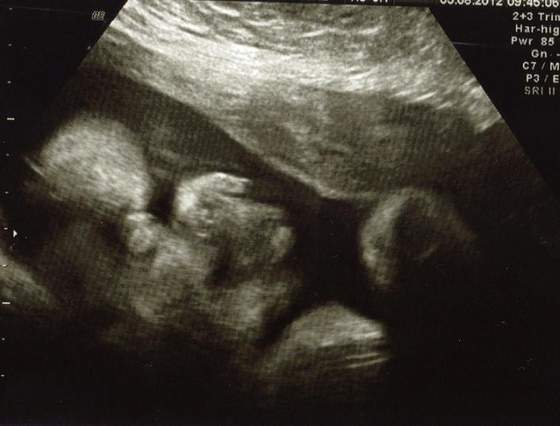

A to buzka mojej Coreczki

zadarty nosek po mamusi